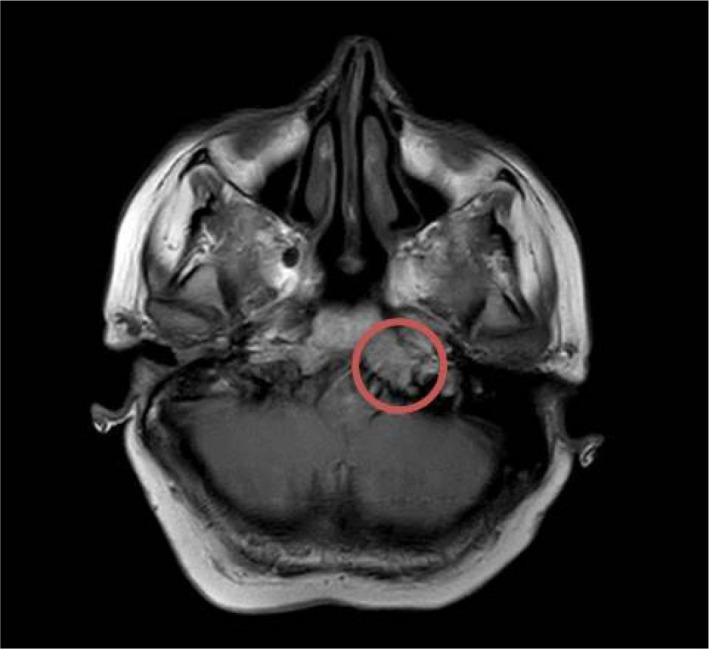

Hepatocellular cancer (HCC) is the most common primary malignant tumor of the liver. The organs that HCC most commonly metastasizes to are the lungs, intra-abdominal lymph nodes, bones, and adrenal glands. Brain metastases have been reported rarely. Herein, we report a 54-year-old female patient who was diagnosed with cryptogenic cirrhosis by liver biopsy in 2010. Solid lesions were detected on radiological examination during follow-up in 2019. The patient's complaints of severe headache, nausea, and vomiting continued during the follow-up, and imaging was performed. A contrast-enhancing lesion, 2 cm in size, was reported in the left half of the clivus on T1 examination after intravenous contrast administration. A biopsy was performed on the mass extending from the clivus to the nasopharynx. The biopsy concluded that it was an HCC metastasis. Intracranial metastases of HCC have been reported very rarely compared to other extrahepatic sites. HCC cases with intracranial metastases have a poor prognosis. Intracranial metastases should be considered in the differential diagnosis in patients presenting with central nervous system findings.